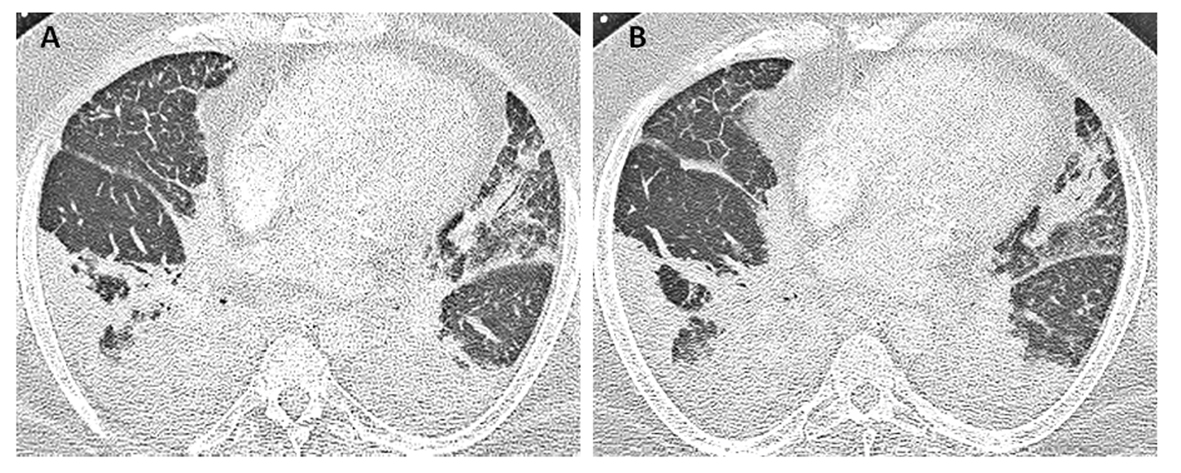

Laboratory studies were significant for anemia with hemoglobin at 11 (12 - 15.5 g/dL) and leukocytosis with WCC 15.41 (3 - 11 × 103 mL). His creatinine was 0.67 (0.3 - 1.2 mg/dL) and B natriuretic peptide level was within normal limit at 53 (0 - 99 pg/mL). Chest X-ray showed bilateral perihilar haziness, consistent with pulmonary edema (Fig. 1). His electrocardiogram revealed sinus tachycardia with right bundle branch block. An echocardiogram demonstrated a good left and right ventricular systolic function (left ventricular ejection fraction 59%), grade-1 diastolic dysfunction with trivial tricuspid regurgitation. A diagnosis of diastolic heart failure was considered and patient was treated with diuretics, aiming daily negative fluid balance of 500 - 1,000 mL. He had lost 2 kg of weight since admission within a week with improvement of his pedal edema. However his breathing continued to deteriorate even after aggressive diuresis. On the seventh day of admission, he became tachypneic and hypoxic with arterial blood gas showing hypoxic and hypercarbic respiratory failure (pH 7.28, pO2 78 mm Hg and pCO2 76 mm Hg on FIO2 of 1.0). A repeat chest X-ray revealed diffuse bilateral infiltrates, predominantly interstitial in character, worsened compared to previous chest X-ray (Fig. 2). He required intubation and support with mechanical ventilation. Patients CT scan of chest (Fig. 3) demonstrated mediastinal lymphadenopathy, diffuse pulmonary nodules, multifocal infiltrates worse in right upper lobe, lower lobe, lingular lobe, and left lower lobe as well as bilateral pleural effusion.

![]() Click for large image | Figure 3. Patient’s CT scan of chest on day 7 (A, B) demonstrated mediastinal lymphadenopathy, diffuses pulmonary nodules, multifocal consolidations in right upper and lower lobe, lingular lobe, and left lower lobe as well as bilateral pleural effusion. |